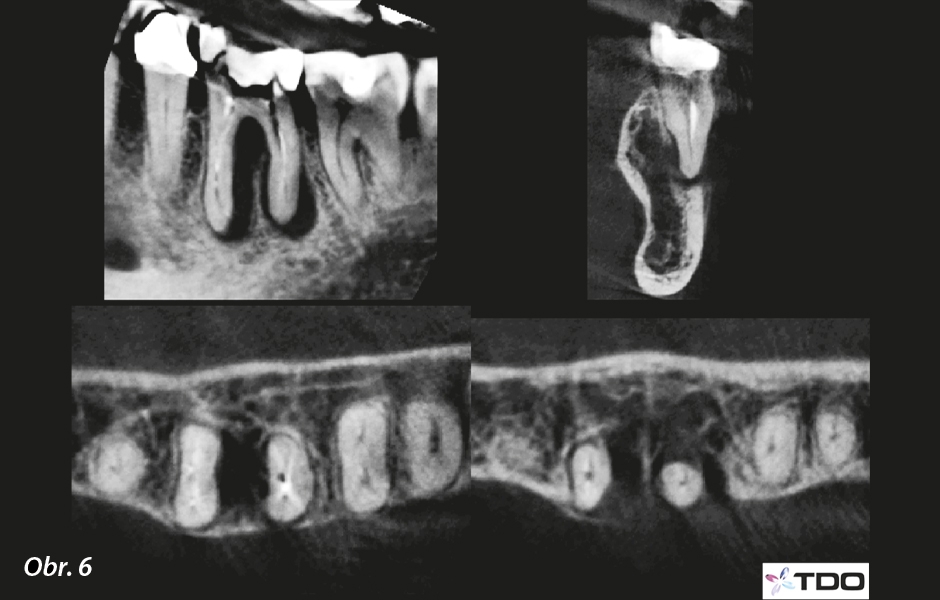

U 77leté pacientky se objevily bolesti a otoky související s dolním levým prvním molárem. Již dříve byla v péči dvou endodontistů, kterým se nepodařilo její příznaky zmírnit (obr. 5a, b). Vyšetření odhalilo otok v přilehlé části bukálního vestibula a zub byl citlivý na poklep. Hloubky při sondování gingiválního sulku byly normální, s výjimkou úzkého 7mm chobotu z bukální strany meziálního kořene. Transiluminace neukázala žádné příznaky prasklého zubu. Radiologické vyšetření ukázalo radiolucenci ve tvaru písmene J u meziálního kořene a menší apikální radiolucenci u distálního kořene. CBCT sken potvrdil rozsah nálezů a také ukázal úbytek bukální lamely u distálního kořene (obr. 6). Byla stanovena diagnóza symptomatické apikální periodontitidy s bukální píštělí podél parodontální štěrbiny.

Řezy z CBCT zachycující nález ve tvaru písmene J u meziálního kořene a menší apikální nález u distálního kořene